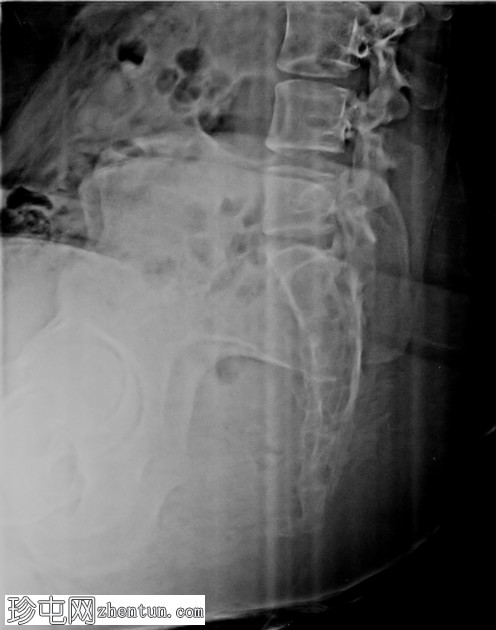

侧位片

远端尾骨节段相对于正常排列呈前倾角增大。未见急性骨折线或脱位。未见局灶性溶骨性或硬化

性病

变,提示无

肿瘤

。

侧位尾骨X线片是评估排列情况并排除骨折/脱位的首选

影像

前倾角增大但无骨折支持机械性尾骨痛的诊断。